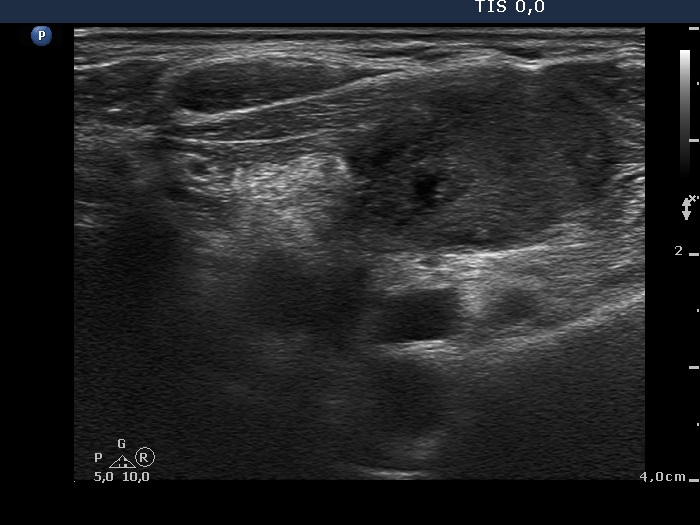

Ultrasonography. There was a moderately hypoechogenic nodule presenting halo sign and perinodular blood flow in the right while two smaller lesions in the left lobe. One of the latter displayed multiple microcalcifications.

The mass in the left side of the neck corresponded to a conglomerate of multiple lymph nodes. These were irregular in shape and presented cystic and necrotic areas. There was no hilum present. The lymph nodes were avascular.